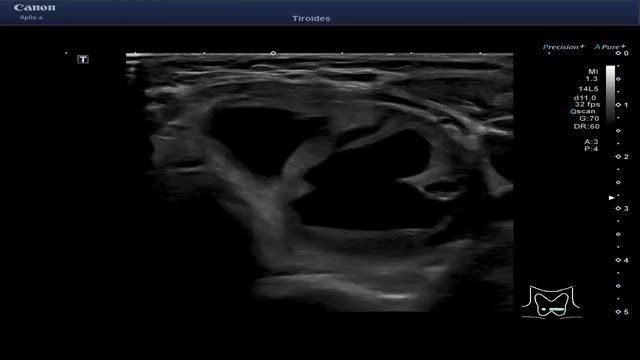

≥7 puntos: TIRADS 5 (probabilidad de malignizar >20%). Clasifica el nódulo como altamente sospechoso. Se realizará seguimiento si el nódulo es ≥5mm y PAAF si el nódulo es ≥10mm (fig. 6 y video 5)

Figura 6.TI-RADS 5 A: Nódulo sólido hipoecoico, mal delimitado, de márgenes mal definidos, con morfología «más alto que ancho» y con microcalcificaciones. B: Nódulo sólido muy hipoecoico, de márgenes bien definidos, con microcalcificaciones, que se agrupan en el borde inferior del nódulo y dejan algo de sombra posterior.